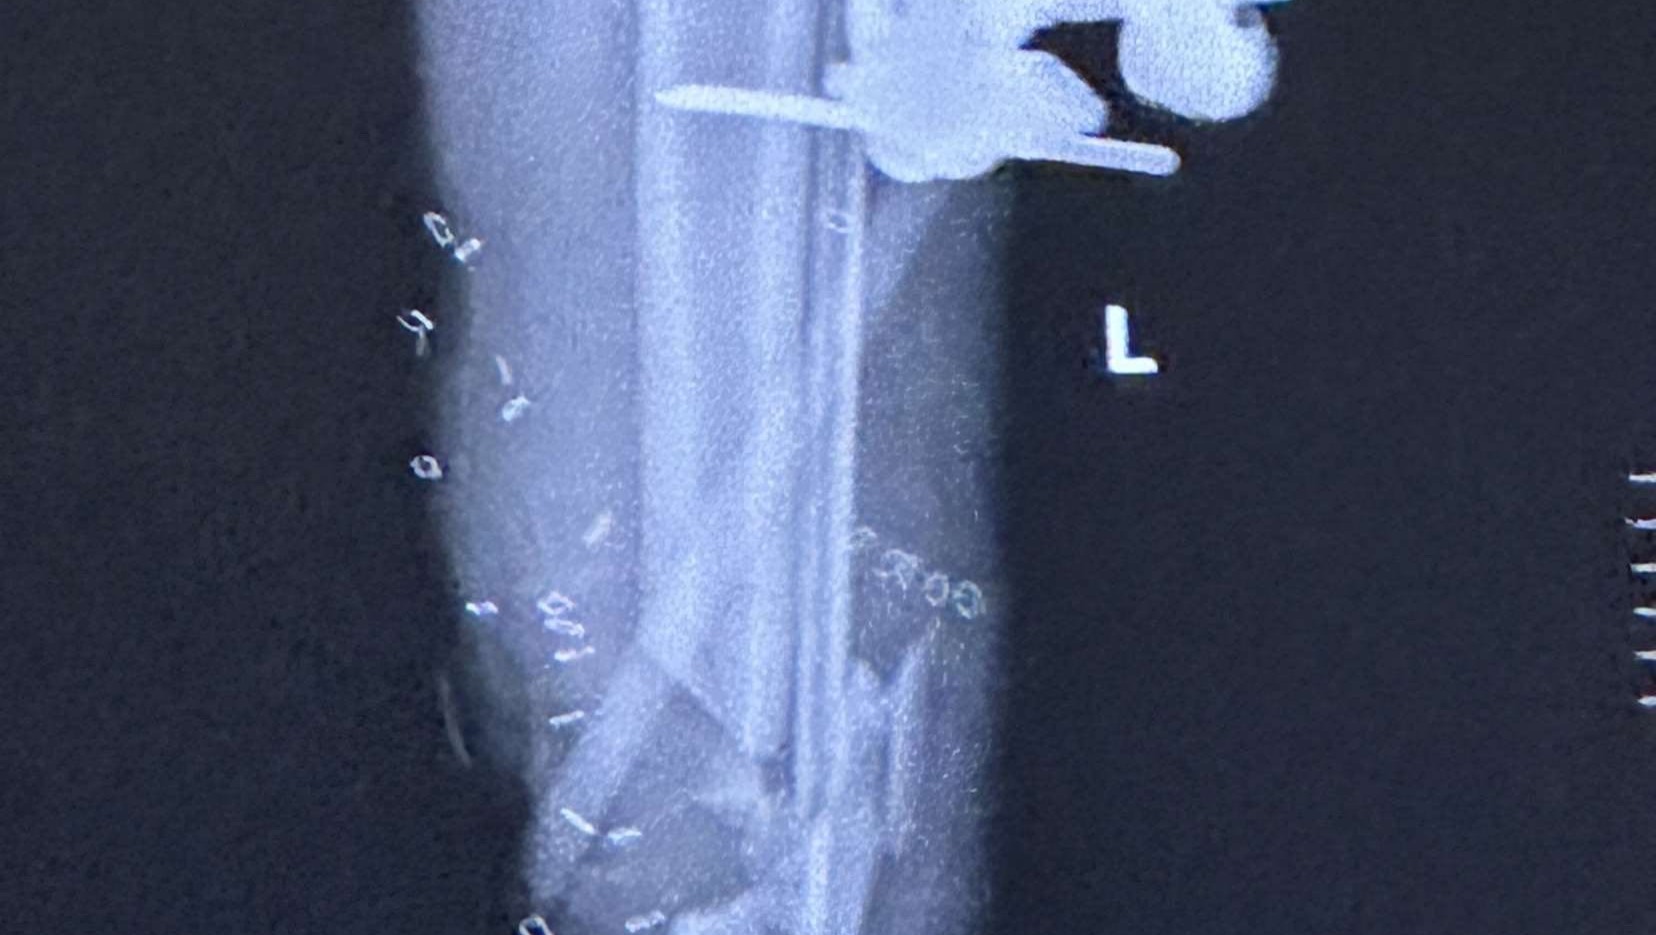

Hi, I'm Paul Koenig, a family friend of Matt Ward, who was in a serious motorcycle accident, being hit by a minivan. He's currently laid up in the hospital with a broken leg and has undergone two major surgeries for limb salvage/reconstruction. Matt still has numerous upcoming surgeries to save and rebuild his left leg. He's asking for donations to help with impending medical expenses. He's due to graduate from high school this year and was enrolled in trade school starting in July to become an automotive mechanic. With this accident, those plans might be delayed, and he needs help to get through this challenging time.